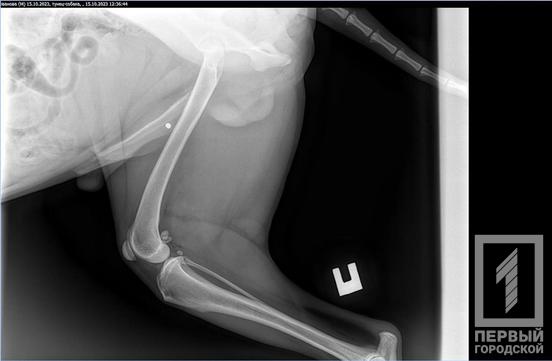

Рентген показав застряглу кулю в лапі. Далі песик отримає необхідну допомогу.